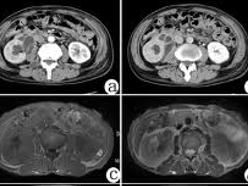

3.CT掃描檢查

可顯示腎內多個結節狀或較大腫塊樣低密度病灶,並可見腎盂或集合管系統的結石和鈣化灶;也可表現為腎一極增大變形或局限性腎腫塊,等密度或略高密度,但增強後強化不明顯;有時可侵犯腎周間隙和腰大肌。

4.磁共振(MRI)和B超檢查

也有助於診斷,B超檢查可見腎臟增大,腎內見液性暗區。